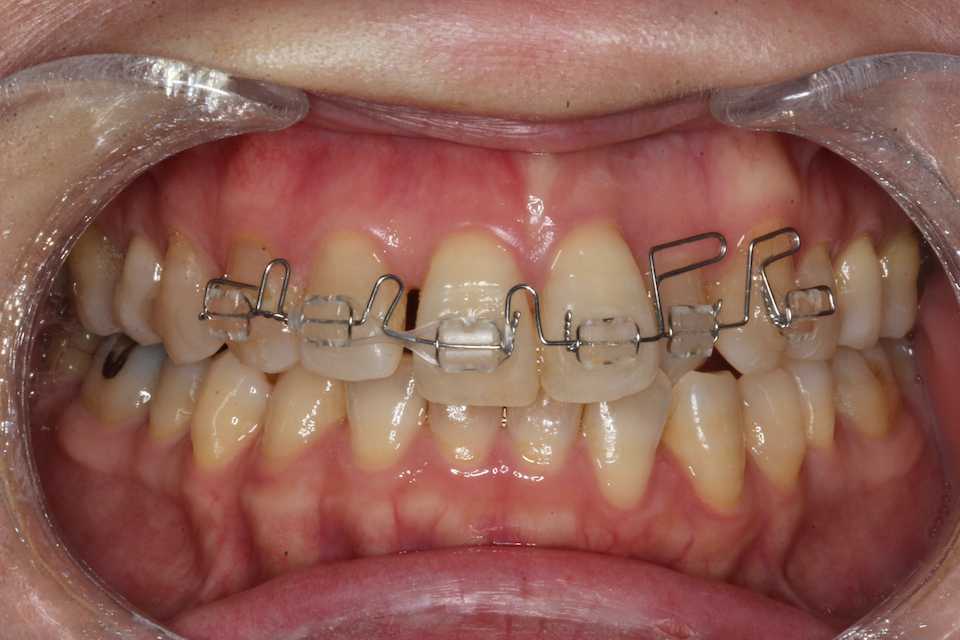

隙間をパワーチェインで引っ張って寄せる

2025/05/20

左上2番の先が引っかかっているので、太めの丸ワイヤー016"に交換した。